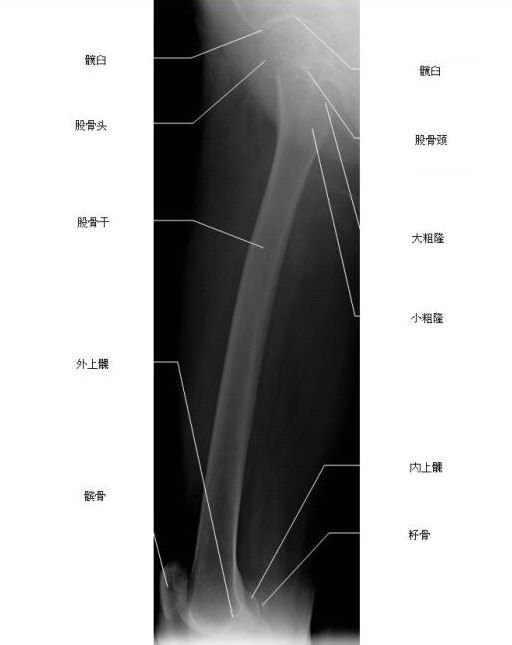

股骨侧位X线片